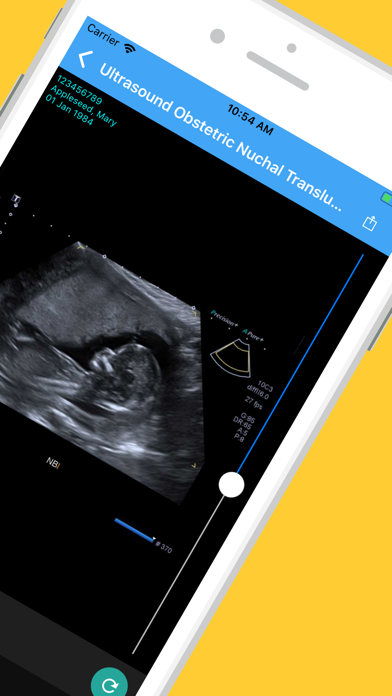

The Infinity Medical Imaging App is used by patients to securely access images and reports

for medical imaging examinations performed at our practice in Chatswood.

Ảnh chụp màn hình của Infinity Medical Imaging App